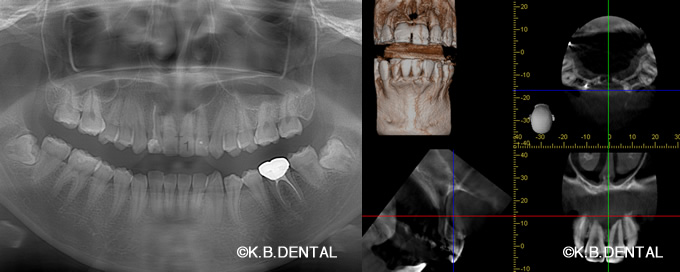

正中過剰埋伏歯(せいちゅうかじょうまいふくし)

正中過剰埋伏歯 症例

正中過剰埋伏歯の症例です。鼻腔底直下にあるので、静脈内鎮静を使い無痛抜歯で対応しました。抜歯が怖い方はご相談下さい。

料金は保険適用で約10,000円の治療費用です。